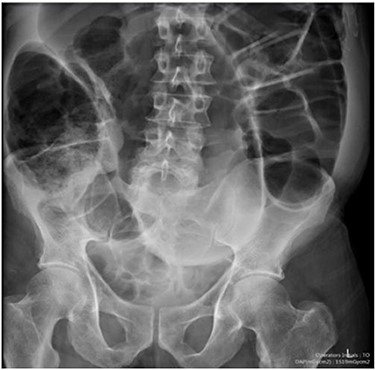

Blood tests on admission were unremarkable. Each admission, the patient’s plain abdominal films showed dilated large bowel loops consistent with sigmoid volvulus (Fig. 1). A subsequent computed tomography (CT) of the abdomen and pelvis with intravenous contrast revealed dilated large bowel and was reported as sigmoid volvulus with no evidence of perforation (Fig. 2). Caecal volvulus was not appreciated on this scan.

Case one: coronal slice of a CT scan of the abdomen and pelvis with intravenous contrast showing dilated large bowel.